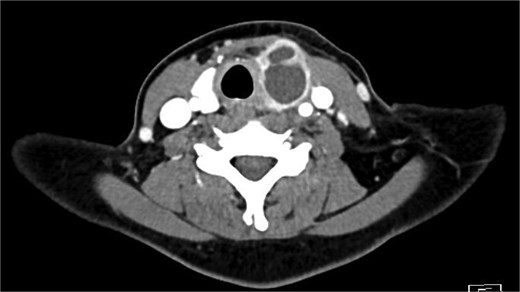

Bloods demonstrated elevated inflammatory markers with a neutrophil count of 7.53 and C-reactive protein of 137. Her biochemistry panel including thyroid function tests were within normal limits. An ultrasound (USS) was performed which showed a cystic/solid nodule in the left thyroid gland that measured 30 × 42 × 22 mm with an estimated volume of 14 ml (Fig. 1). A computed tomography (CT) scan was conducted to ensure no airway compression, it demonstrated the abscess to measure 32 × 26 × 32 mm (Figs 2 and 3). There was no tracheal compression but there was mild inflammatory stranding and hyperenhancement of the nodule consistent with infection.

Sagittal portal venous phase CT of the neck demonstrating the cystic lesion in the left thyroid gland.